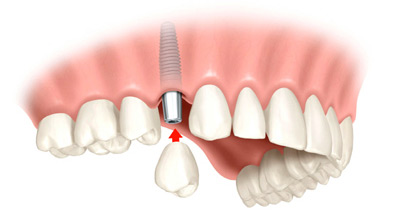

Implantul dentar de care veti beneficia in cadrul cabinetului doctorului Loreta Tohaneanu reprezinta in fapt inserarea unei radacini artificiale, din titan sau zirconiu, ce inlocuieste radacina naturala a dintelui si care are ca scop crearea suportului pentru realizarea de coroane sau punti dentare, atunci cand pe arcada nu mai sunt prezenti dinti sau cand cei prezenti nu se califica pentru un tratament dentar de succes. Practic, implantul dentar se prezinta sub forma unui “surub”, cu un relief divers, in functie de categoria din care face parte si de producator. Fixarea dintilor parodontotici se efectueaza numai cu sisteme adezive moderne. In plus in cadrul cabinetului se efectueaza si proceduri de aditie osoasa preimplantara, reconstructie osoasa, lucrari ceramice fara metal construite pe pivoti din fibra de sticla.

Principalul rol al lucrarilor pe implanturi dentare este de a inlocui dintii lipsa preluand principalele functii ale acestora. Astfel, cu noul implant veti putea mesteca din nou, exact ca inainte cu dintii nativi. Totodata, lucrarile pe implanturi au o estetica deosebita. Acest lucru se datoreaza inlocuirii mult mai aproape de natural a dintilor lipsa comparativ cu o proteza, de exemplu.